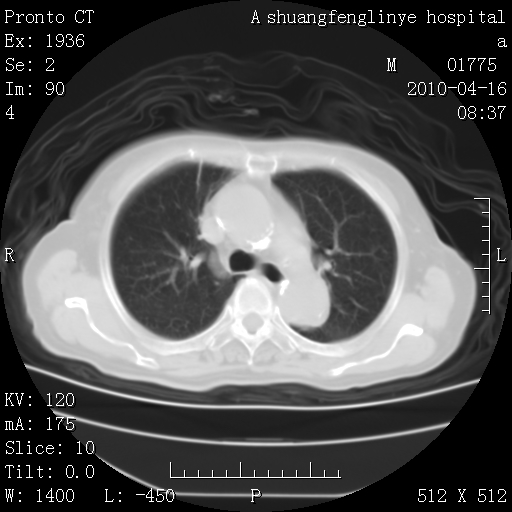

标题: CT25784:咳痰、请会诊!结核? [打印本页]

标题: CT25784:咳痰、请会诊!结核?

考虑左肺上叶增殖灶、纤维灶。

慢支肺气肿,左上陈旧性结核,主动脉冠脉钙化

1)左肺上叶结核(纤维、增殖病灶)。2)冠状动脉及主动脉钙化。

1)左肺上叶结核(纤维、增殖病灶)。2)冠状动脉及主动脉钙化。肺动脉高压